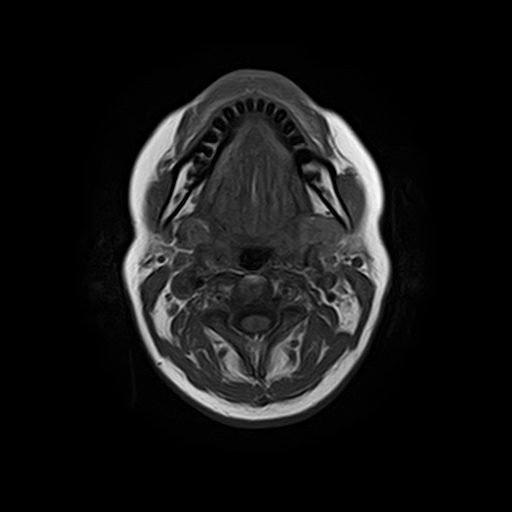

Височно-нижнечелюстной сустав является парным комбинированным суставом и имеет сложное строение. В него входят суставные ямки височной кости, суставные головки нижней челюсти и расположенные между ними хрящевые пластинки – мениски, выполняющие роль амортизаторов.

Чаще всего дисфункция височно-нижнечелюстного сустава обусловлена внутренним повреждением, смещением мениска и суставной головки нижней челюсти. Для определения степени смещения внутрисуставных структур выполняется функциональная проба с проведением МРТ в двух положениях:

• с закрытым ртом;

• с открытым ртом.

Магнитно-резонансная томография является наиболее точным и эффективным методом диагностики поражения височно-нижнечелюстных суставов, так как позволяет получить детальную информацию о состоянии не только костей, но и связочного аппарата, хрящей, менисков, жевательных мышц, окружающих мягких тканей.

При проведении магнитно-резонансной томографии на изображениях визуализируются: височная кость, головка мыщелкового отростка нижней челюсти, суставная щель. Помимо костных структур МРТ позволяет оценить состояние мягких тканей – внутрисуставного диска и связочного аппарата височно-нижнечелюстного сустава, жевательных мышц.